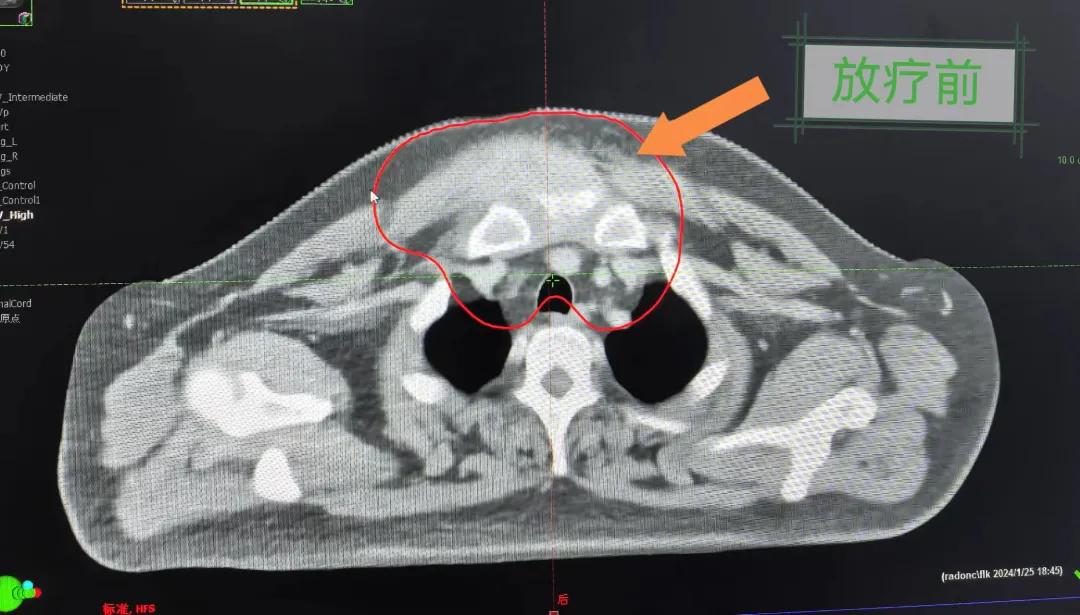

隨后,趙亮主任帶領(lǐng)放療團隊以最快的速度完成了患者的放射治療計劃,在保證放療精準(zhǔn)打擊腫瘤的同時,利用先進的三維立體精確放療技術(shù),最大限度的避免心臟、肺部的損傷發(fā)生,整體治療精準(zhǔn)度達到1mm以內(nèi)。經(jīng)過10次的放射治療后,患者疼痛已明顯減輕,胸部腫物肉眼可見的縮小,患者及家屬臉上終于露出久違的笑臉。

治療期間,患者沒有出現(xiàn)明顯不適,治療結(jié)束后,患者胸壁腫物由最初8cm縮小至約1cm,后患者至外科行手術(shù)治療。